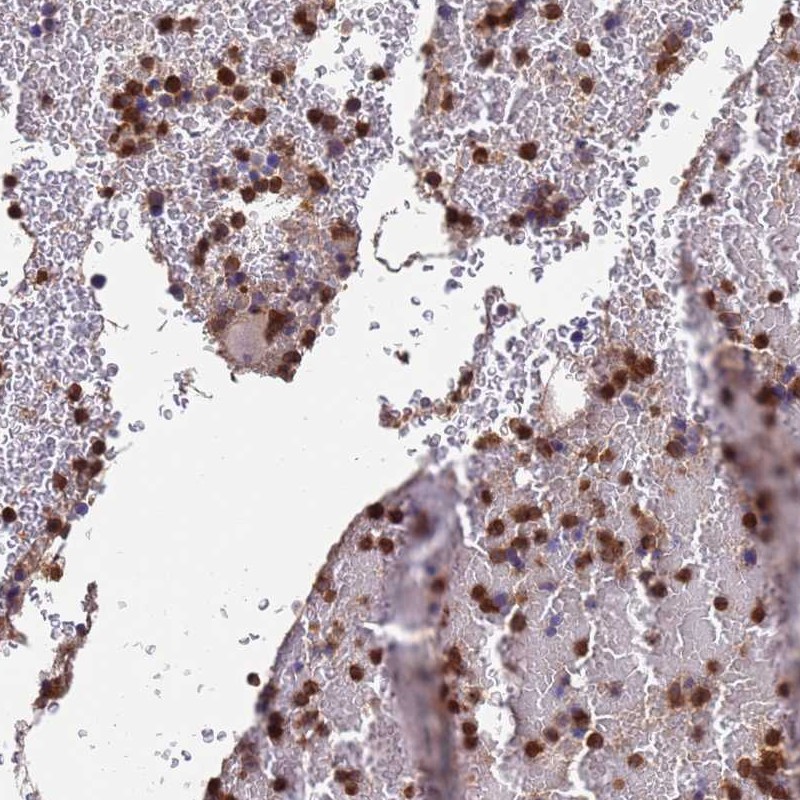

Immunohistochemical staining of human bone marrow shows strong cytoplasmic positivity in hematopoietic cells.